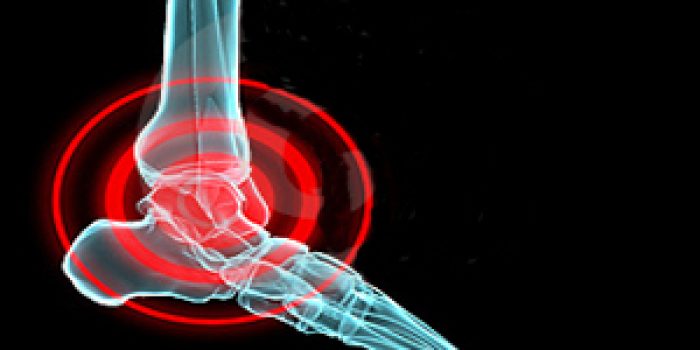

آرتریت که به شکل های مختلف بروز می کند شامل التهاب مفاصل است

اوستئوآرتریت، آرتریت روماتوئید و نقرس ۳ نوع از شایعترین اشکال آرتریت در بین افراد سالمند هستند. اوستئوآرتریت البته از دو نوع دیگر شایعتر است اما هیچکدام از این عارضهها مسری و واگیردار نیستند.

پوکی استخوان زمانی رخ میدهد که غضروفها رو به تخریب میگذارند.در این حالت نرمی استخوان و درد ایجاد میشود.این بیماری زنان و مردان را مبتلا میکند،در افراد بالای ۶۵ سال در بیش از ۵۰ درصد موارد،ابتلا به این عارضه حداقل در یک مفصل رخ میدهد.

درمان این عارضه شامل ورزش،مراقبت از مفاصل،رژیم غذایی مناسب،دارو و جراحی است. برای بهبود درد نیز معمولا استامینوفن تجویز میشود. اوستئوآرتریت ممکن است در هر مفصلی بروز کند اما معمولا آنهایی را تحت تاثیر قرار میدهد که وزن بدن را تحمل میکنند. معمولترین علائم این عارضه شامل درد مفاصل ،ورم مفاصل و نرمی و خمیدگی آنها است. فقط در یک سوم موارد افرادی که با پرتو ایکس بیماری آنها تشخیص داده میشود فاقد علائم ظاهری هستند.